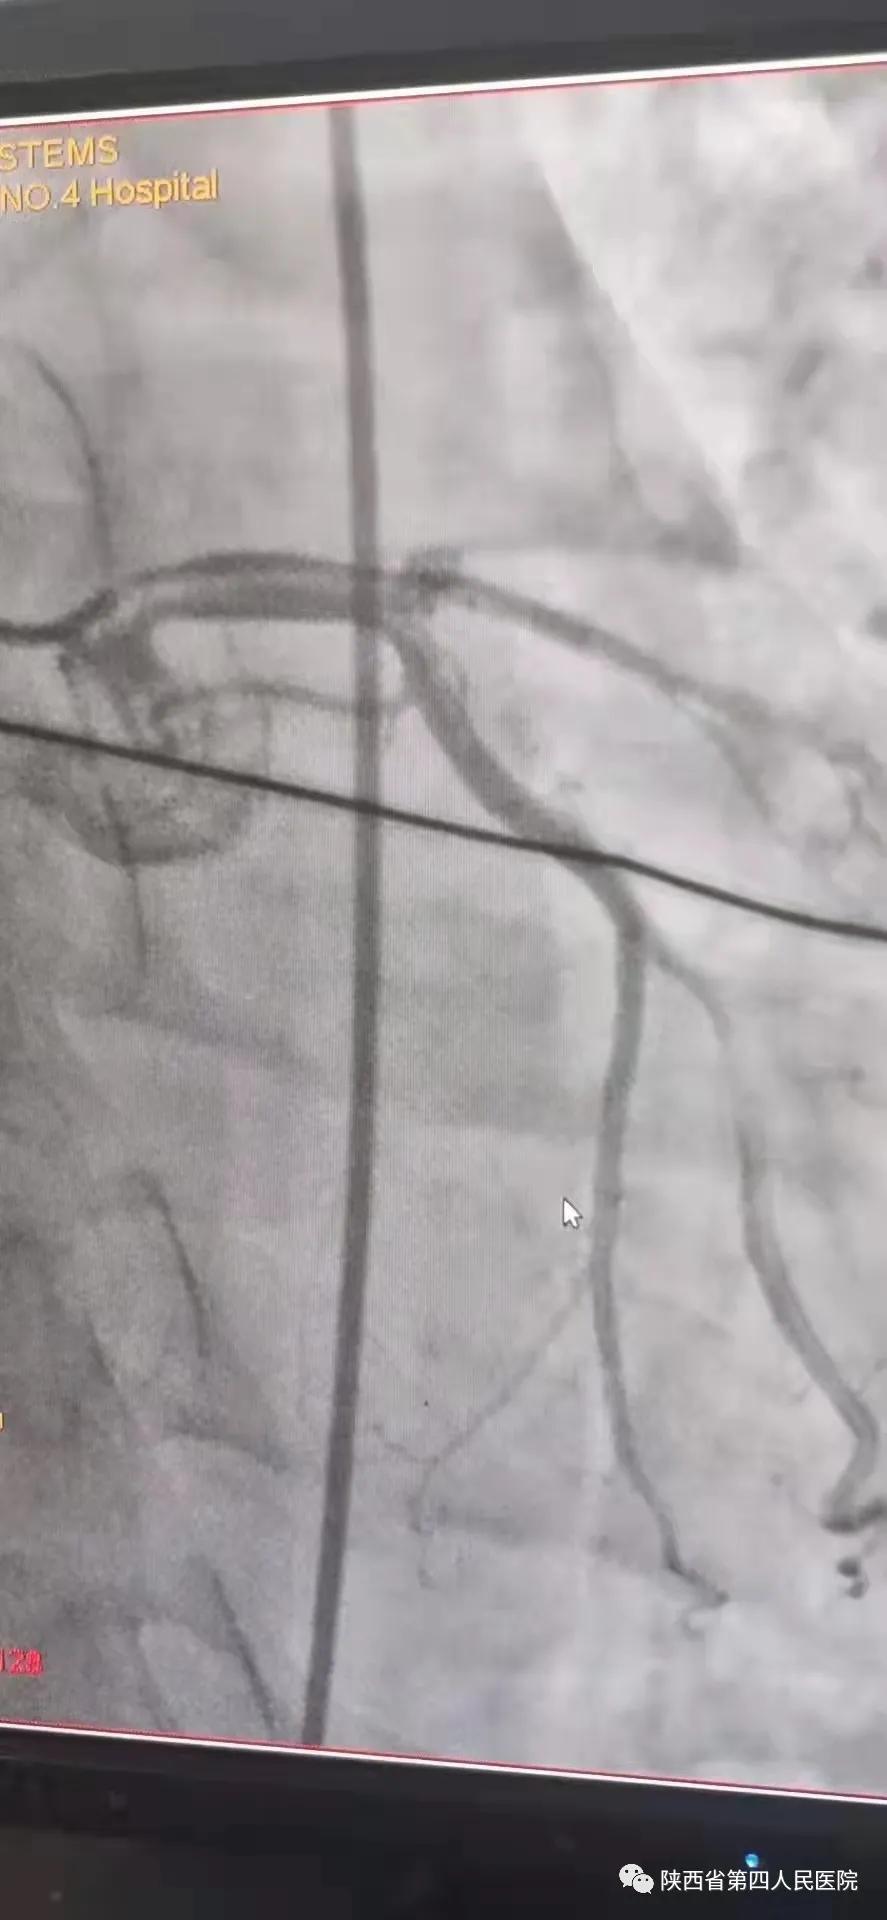

11月10日15时58分左右 , 家住医院附近的中年男性辛先生在家人陪伴下来到陕西省第四人民医院急诊内科门诊诊室 , 满头大汗 , 捂着胸口说胸痛、胸闷、气短 , 急诊科主治医师钟高亮立即安排床位进行留观给予吸氧、心电监护、查体 , 心电图提示:1、窦性心律;2、室性早搏;3、急性下壁、前壁心肌梗死 , 诊断:急性冠脉综合征、心肌梗死 。 随后患者在急诊科留观室病情突然加重 , 意识丧失、四肢抽搐、面色苍白、全身大汗、呼吸急促 , 心电监护提示心室颤动 , 判断其可能为急性心肌梗死心源性休克 , 急诊科和心内科医生立即行胸外心脏按压 , 电除颤三次等对症治疗 , 立即启动胸痛患者抢救应急预案 , 开启绿色通道 , 和患者家属谈话 , 为其迅速办理入院手续 , 给予升压补液扩容等抢救治疗 , 积极完善术前准备 , 联系医务科和介入导管室 , 于16时22分将患者转运至导管室 , 心内科主任、主任医师王选琦和团队副主任医师孙耀林、王崇振 , 主治医师马艳萍共同夺取患者最宝贵生命时间 , 为患者选择了从下肢股动脉穿刺造影 , 从穿刺到开通血管用仅仅只用了十一分钟 。 16时33分顺利完成PAG+PCI支架植入术后成功再通 , 患者转危为安 , 随后入住心血管内科CCU病房继续治疗 。

术前